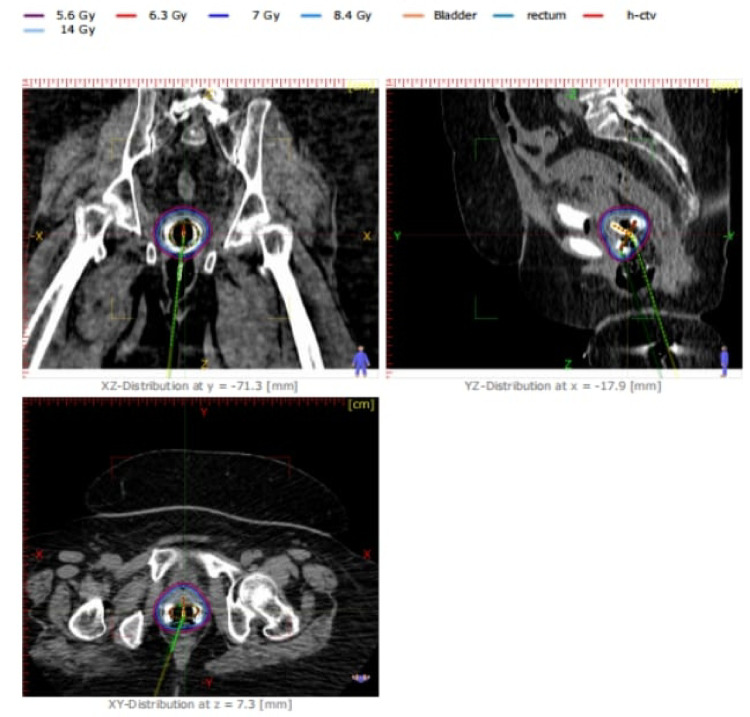

Methods: A retrospective dosimetric analysis was conducted on 30 patients with FIGO stage IIB-IIIB cervical cancer, eligable for Brachytherapy, were treated using CT-guided intracavitary HDR brachytherapy with Co-60 sources. Treatment plans were assessed for high-risk clinical target volume (HR-CTV) coverage (D90, D80), dose-volume histogram parameters, and organ-at-risk (OAR) doses (D2cc for bladder, rectum, and sigmoid). Plan quality indices including conformity index (COIN), dose homogeneity index (DHI), and dose non-uniformity ratio (DNR) were calculated. Uncertainty analyses accounted for treatment planning system (TPS) variability and applicator positioning.

Results: The mean HR-CTV D90 was 6.97 Gy, achieving 99.6% of the prescription dose. The mean D2cc values were 5.73 Gy for bladder (81.9%Rx), 4.72 Gy for rectum (67.4%Rx), and 3.23 Gy for sigmoid, all within acceptable tolerance limits. The mean COIN was 0.292, DHI 0.31, and DNR 0.69, indicating moderate dose conformity and acceptable inhomogeneity. TPS and applicator uncertainties contributed to estimated dose deviations of ± 2% and ± 1 mm, respectively.